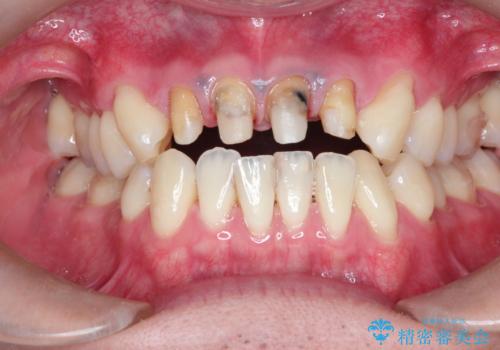

- 上の前歯の見た目が気になるとのことで来院されました。

上の前歯の4本が神経の処置がされており、前から2番目の歯が内側に入り込んでしまっていました。

また、金属で治療された根本の歯茎が黒く変色(メタルタトゥー)しており、余計に見た目がよくない状態となっておりました。